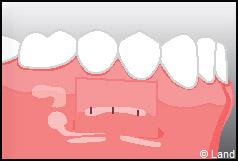

LES TECHNIQUES SANS APPORT DE GENCIVE :

Elles font appel à des lambeaux de gencive restante à proximité des récessions, qui sont déplacés et repositionnés sur la récession.

LES TECHNIQUES AVEC APPORT DE GENCIVE OU « GREFFE DE GENCIVE » :

Elles font appel à un prélèvement sur le patient à un endroit où elle est en excès, qui est ensuite posé sur la récession.